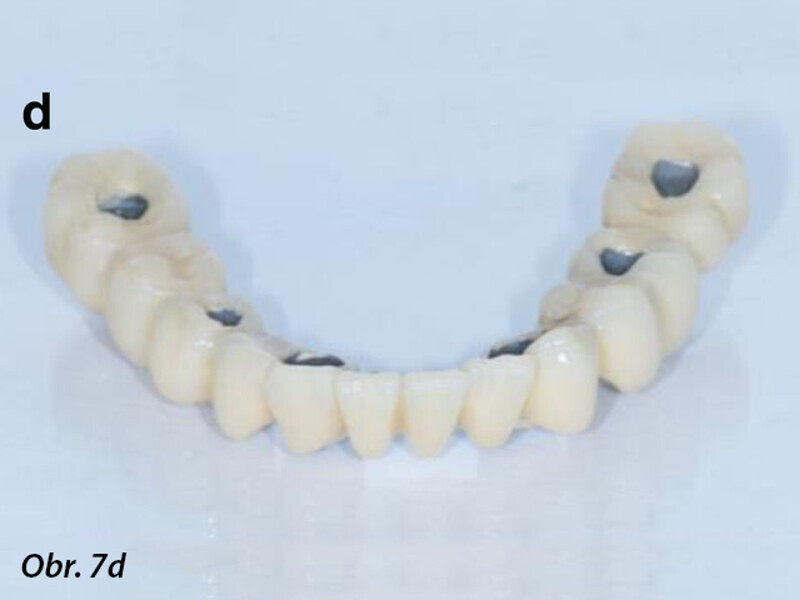

Počítačem asistované, šablonou se řídící okamžité zavedení a zatížení implantátu v dolní čelisti